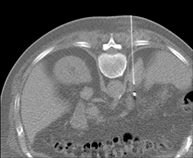

- PAAF (Punción) Tórax guiada por TC Prueba que consiste en obtener una muestra de tejido de lesiones torácicas, como por ejemplo masas pulmonares, mediastínicas, lesiones óseas, etc. Para ello se administra anestesia local sobre la zona de la punción, la cual se realiza con agujas de fino calibre. Todo el procedimiento se realiza controlado por imágenes obtenidas por Tomografía Computarizada (TC) en varios momentos de la punción, mediante un equipo de Fluoroscopia-TC. Tras la prueba, el paciente permanece unas horas hospitalizado. Es necesario aportar pruebas de coagulación antes de la punción. Prueba que consiste en obtener una muestra de tejido de lesiones torácicas, como por ejemplo masas pulmonares, mediastínicas, lesiones óseas, etc. Para ello se administra anestesia local sobre la zona de la punción, la cual se realiza con agujas de fino calibre. Todo el procedimiento se realiza controlado por imágenes obtenidas por Tomografía Computarizada (TC) en varios momentos de la punción, mediante un equipo de Fluoroscopia-TC. Tras la prueba, el paciente permanece unas horas hospitalizado. Es necesario aportar pruebas de coagulación antes de la punción.

- PAAF (Punción) Abdominal guiada por TC Consiste en obtener una muestra de tejido de una determinada lesión localizada en la cavidad abdominal. Para ello se administra anestesia local sobre la zona de la punción, la cual se realiza con agujas de fino calibre. Todo el procedimiento se realiza controlado con imágenes obtenidas por Tomografía Computarizada (TC) en varios momentos de la punción, mediante el uso de un equipo de Fluroscopia-TC. Tras la prueba, el paciente permanece unas horas hospitalizado para controlar su evolución. Es necesario aportar pruebas de coagulación antes de la punción. Consiste en obtener una muestra de tejido de una determinada lesión localizada en la cavidad abdominal. Para ello se administra anestesia local sobre la zona de la punción, la cual se realiza con agujas de fino calibre. Todo el procedimiento se realiza controlado con imágenes obtenidas por Tomografía Computarizada (TC) en varios momentos de la punción, mediante el uso de un equipo de Fluroscopia-TC. Tras la prueba, el paciente permanece unas horas hospitalizado para controlar su evolución. Es necesario aportar pruebas de coagulación antes de la punción.